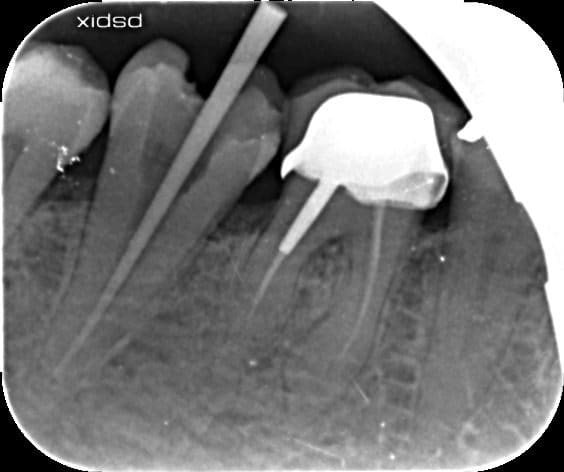

ENdo fait le 12/11/15

Pose inlay core + prov le 17/12/15

pose de la ccm le 04/02/16

il a mal depuis la pose de la ccm. Fichtre!

mais c'est vrai qu'il ne se plaint quasiment que de douleurs a la percussion vestibulaire de 47, quasi rien coté lingual.